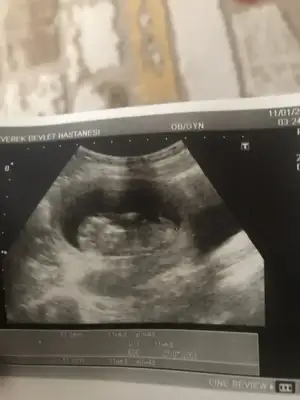

Kızlar 11+6 benimkileride yorumlayabilirmisiniz çok merak ettim :)

Eklentiler

• 84FE723F-22F5-4A55-834C-3693899F41CC.webp

84FE723F-22F5-4A55-834C-3693899F41CC.webp

29,5 KB · Görüntüleme: 55

• 4F30DDF2-88EA-4F7B-B3D9-93327EE510AC.webp

4F30DDF2-88EA-4F7B-B3D9-93327EE510AC.webp

39,1 KB · Görüntüleme: 56